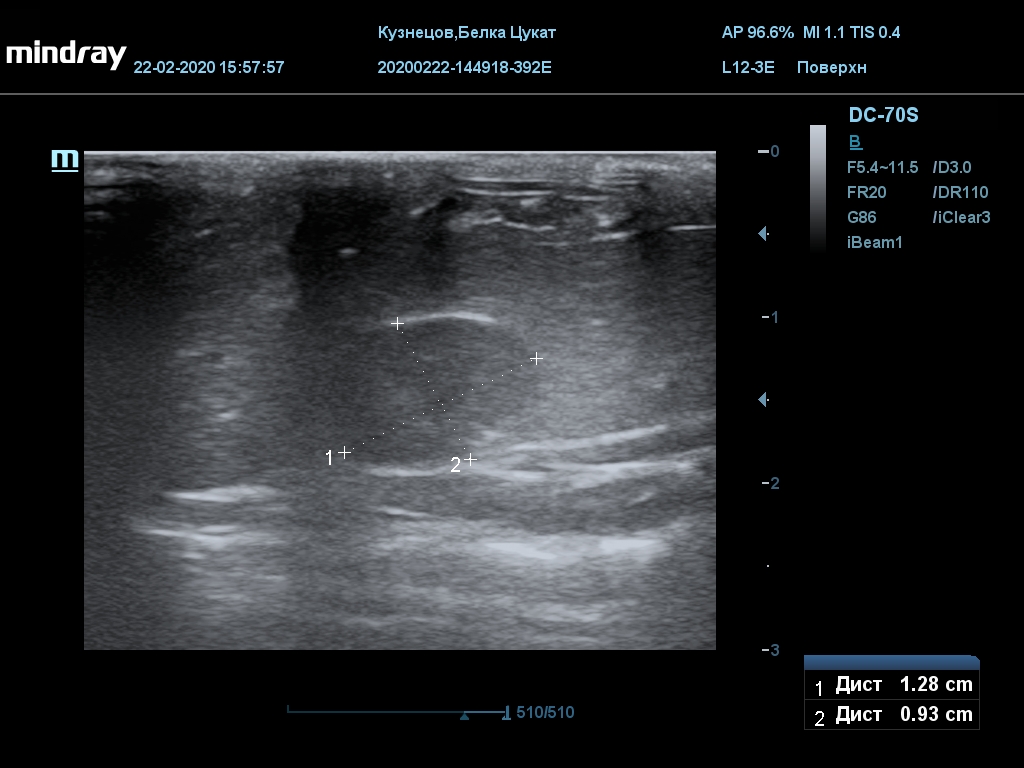

УЗИ

(почки, мочевой пузырь и, предположительно, простата)

Обращаю внимание, что делала УЗИ и писала заключение узист, которая специализируется на кошках и собаках, поэтому она сделала узи и описала, как смогла, но тонкостей грызунячьей анатомии она не знает.

Приложил только фото, есть ещё пара видео, но не знаю, как тут выложить, и надо ли.

Мочевой пузырь объём 12,1 х 7,6 х 11 мм. Стенка не утолщена, 0,5 мм, содержимое не однородное, до половины объёма гипоэхогенная мелкодисперсная взвесь. Макс. размер включений 0,8 мм. Теней нет.

Каудальнее мочевого пузыря визуализируется округлая структура размером 11,1 х 8,3 мм с ровными контурами гипоэхогенная однородная, с признаками васкуляризации.

Почка левая ровная, размер 12 х 7,6 х 8,2 мм. Контур ровный чёткий. КМД отсутствует, лоханка расширена незначительно, объёмных включений не выявлено.

Почка правая ровная, контур чёткий, размер 13,5 х 8,7 х 9,3 мм. Капсула визуализируется. КМД отсутствует, лоханка не расширена. Объёмные образования не выявлены.

Заключение: УЗпризнаки уролитиаза, объёмная структура каудальнее мочевого пузыря. Признаки расширения левой лоханки.

УЗИ

(почки, мочевой пузырь и, предположительно, простата)

Обращаю внимание, что делала УЗИ и писала заключение узист, которая специализируется на кошках и собаках, поэтому она сделала узи и описала, как смогла, но тонкостей грызунячьей анатомии она не знает.

Приложил только фото, есть ещё пара видео, но не знаю, как тут выложить, и надо ли.

Мочевой пузырь объём 12,1 х 7,6 х 11 мм. Стенка не утолщена, 0,5 мм, содержимое не однородное, до половины объёма гипоэхогенная мелкодисперсная взвесь. Макс. размер включений 0,8 мм. Теней нет.

Каудальнее мочевого пузыря визуализируется округлая структура размером 11,1 х 8,3 мм с ровными контурами гипоэхогенная однородная, с признаками васкуляризации.

Почка левая ровная, размер 12 х 7,6 х 8,2 мм. Контур ровный чёткий. КМД отсутствует, лоханка расширена незначительно, объёмных включений не выявлено.

Почка правая ровная, контур чёткий, размер 13,5 х 8,7 х 9,3 мм. Капсула визуализируется. КМД отсутствует, лоханка не расширена. Объёмные образования не выявлены.

Заключение: УЗпризнаки уролитиаза, объёмная структура каудальнее мочевого пузыря. Признаки расширения левой лоханки.